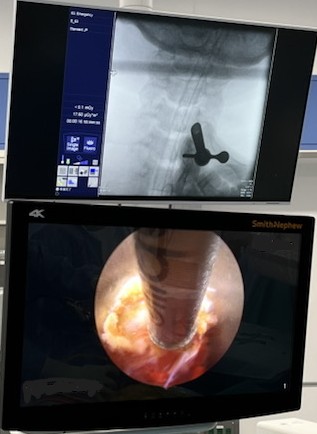

手術ナビゲーションシステムとは

せぼねの手術で用いられるナビゲーションシステムは、手術を安全に行うための機器になります。せぼねの病気はさまざまあり、患者さんによって病気の部位や骨の変形は異なります。また、せぼねの周りには大事な神経組織や血管が位置しているため、これらを傷つけないように手術が行われる必要があります。これまでは透視装置などを駆使して手術が行われていました。しかし、固定術で施行されるスクリューの誤設置や固定材料の不適切な設置がなされる場合がありました。

当院では様々な種類のナビゲーションシステムを採用しています。そのため、手術はより安全に行われ、手術時間の短縮、出血量の低減、被爆量の減少、さらには早期復帰につながるものと考えています。

ナビゲーションシステムを用いた

内視鏡手術

ナビゲーションシステムを用いた内視鏡手術

スクリューを用いた手術

ナビゲーションシステムを用いたスクリューを用いた手術